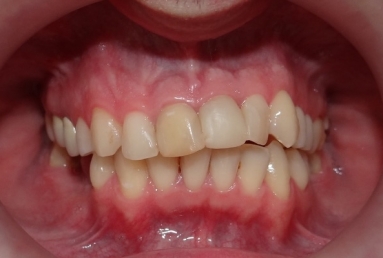

The orthodontic treatment was necessary as the upper maxillary developed assimetricaly, also the teeth were malpositioned. The purpose of the partial braces was to help the final prosthetic treatment, which consisted of two full ceramic crowns for the central incisors, that had root canal treatments, and a ceramic veneer for the lateral incisor, that had a large composite filling. Gingivectomies were also necessary for the right canine and incisors in order to correct the assymetrical gummy smile.